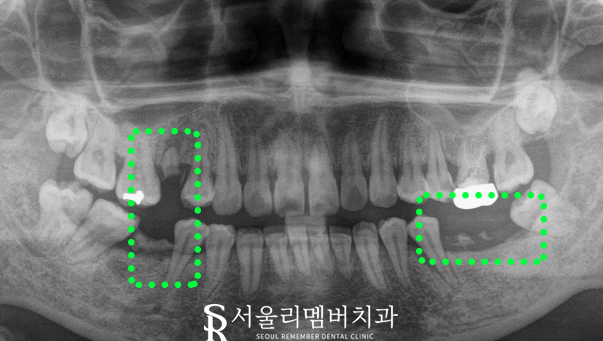

초진 사진 보겠습니다.

x-ray를 보면

어금니가 없습니다.

무슨 문제가 있나요?

그냥 그 자리가 빈자리로 남아있는 게 아니라

주변 인접치, 대합치가 빈자리를

채우려 하는 것이 문제입니다.

그렇게 되면 치열 자체가 틀어지면서

식생활에 필요한 교합이 힘들어지고

제일 문제는 소실된 부위의 치조골이

자극을 못 받아 점차 퇴축되어

잇몸이 아래로 계속 내려가게 됩니다.